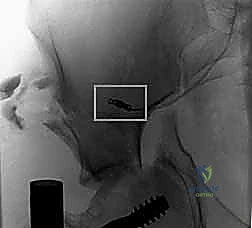

2. الأشعة السينية (X-rays): توفر نظرة أولية سريعة على كسور الحوض (AP, Inlet, and Outlet views).

يتم الاستعانة بجهاز الأشعة السينية المتحرك داخل غرفة العمليات (C-arm Fluoroscopy) للتأكد من وضعية المسامير بدقة المليمتر، لضمان عدم اختراقها للأعصاب أو الأوعية الدموية.